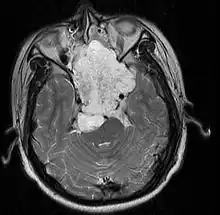

| MRI of extensive clival chordoma in 17-year-old male patient, axial view. Tumor in the nasopharynx extending from nasal cavity to brainstem posteriorly is clearly visible. | |